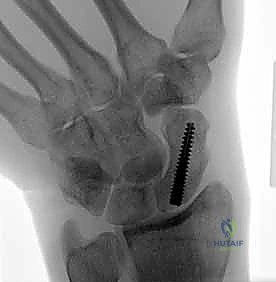

تقنية "التثبيت عن طريق الجلد" (Percutaneous Fixation) هي إجراء جراحي طفيف التوغل (Minimally Invasive). بدلاً من فتح الرسغ، يقوم الجراح بإجراء ثقب صغير جداً في الجلد (لا يتجاوز 3-5 مليمترات). من خلال هذا الثقب، وباستخدام جهاز الأشعة السينية المباشر في غرفة العمليات (C-arm Fluoroscopy)، يتم إدخال سلك توجيهي دقيق، ثم يتم إدخال مسمار خاص يسمى "مسمار ضغط بدون رأس" (Headless Compression Screw) مثل مسمار هيربرت (Herbert Screw).

هذا المسمار العبقري يتم دفنه بالكامل داخل العظم (تحت سطح الغضروف حتى لا يحتك بالمفاصل الأخرى)، ويتميز بوجود أسنان لولبية (Threads) في طرفيه بمسافات مختلفة. هذا التصميم يجعله يسحب طرفي الكسر ويضغطهما معاً بقوة هائلة (Compression)، مما يحفز التئام العظم بسرعة فائقة ويمنع أي حركة بين طرفي الكسر.

يختار الأستاذ الدكتور محمد هطيف المدخل الجراحي بمهارة بناءً على موقع الكسر:

1. المدخل البطني (Volar Approach): من جهة راحة اليد. يُستخدم عادة لكسور منطقة الخصر (المنتصف).